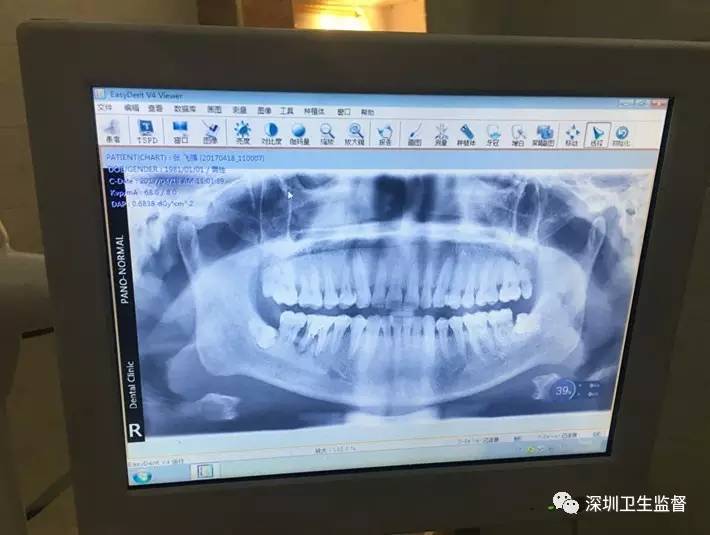

平湖一牙科哭诉亏本:拍个口腔全景片收100块 结果被罚5万多

今年3月,龙岗区平湖街道一口腔门诊部为患者拍牙科全景片,开出了一张100元的收据......